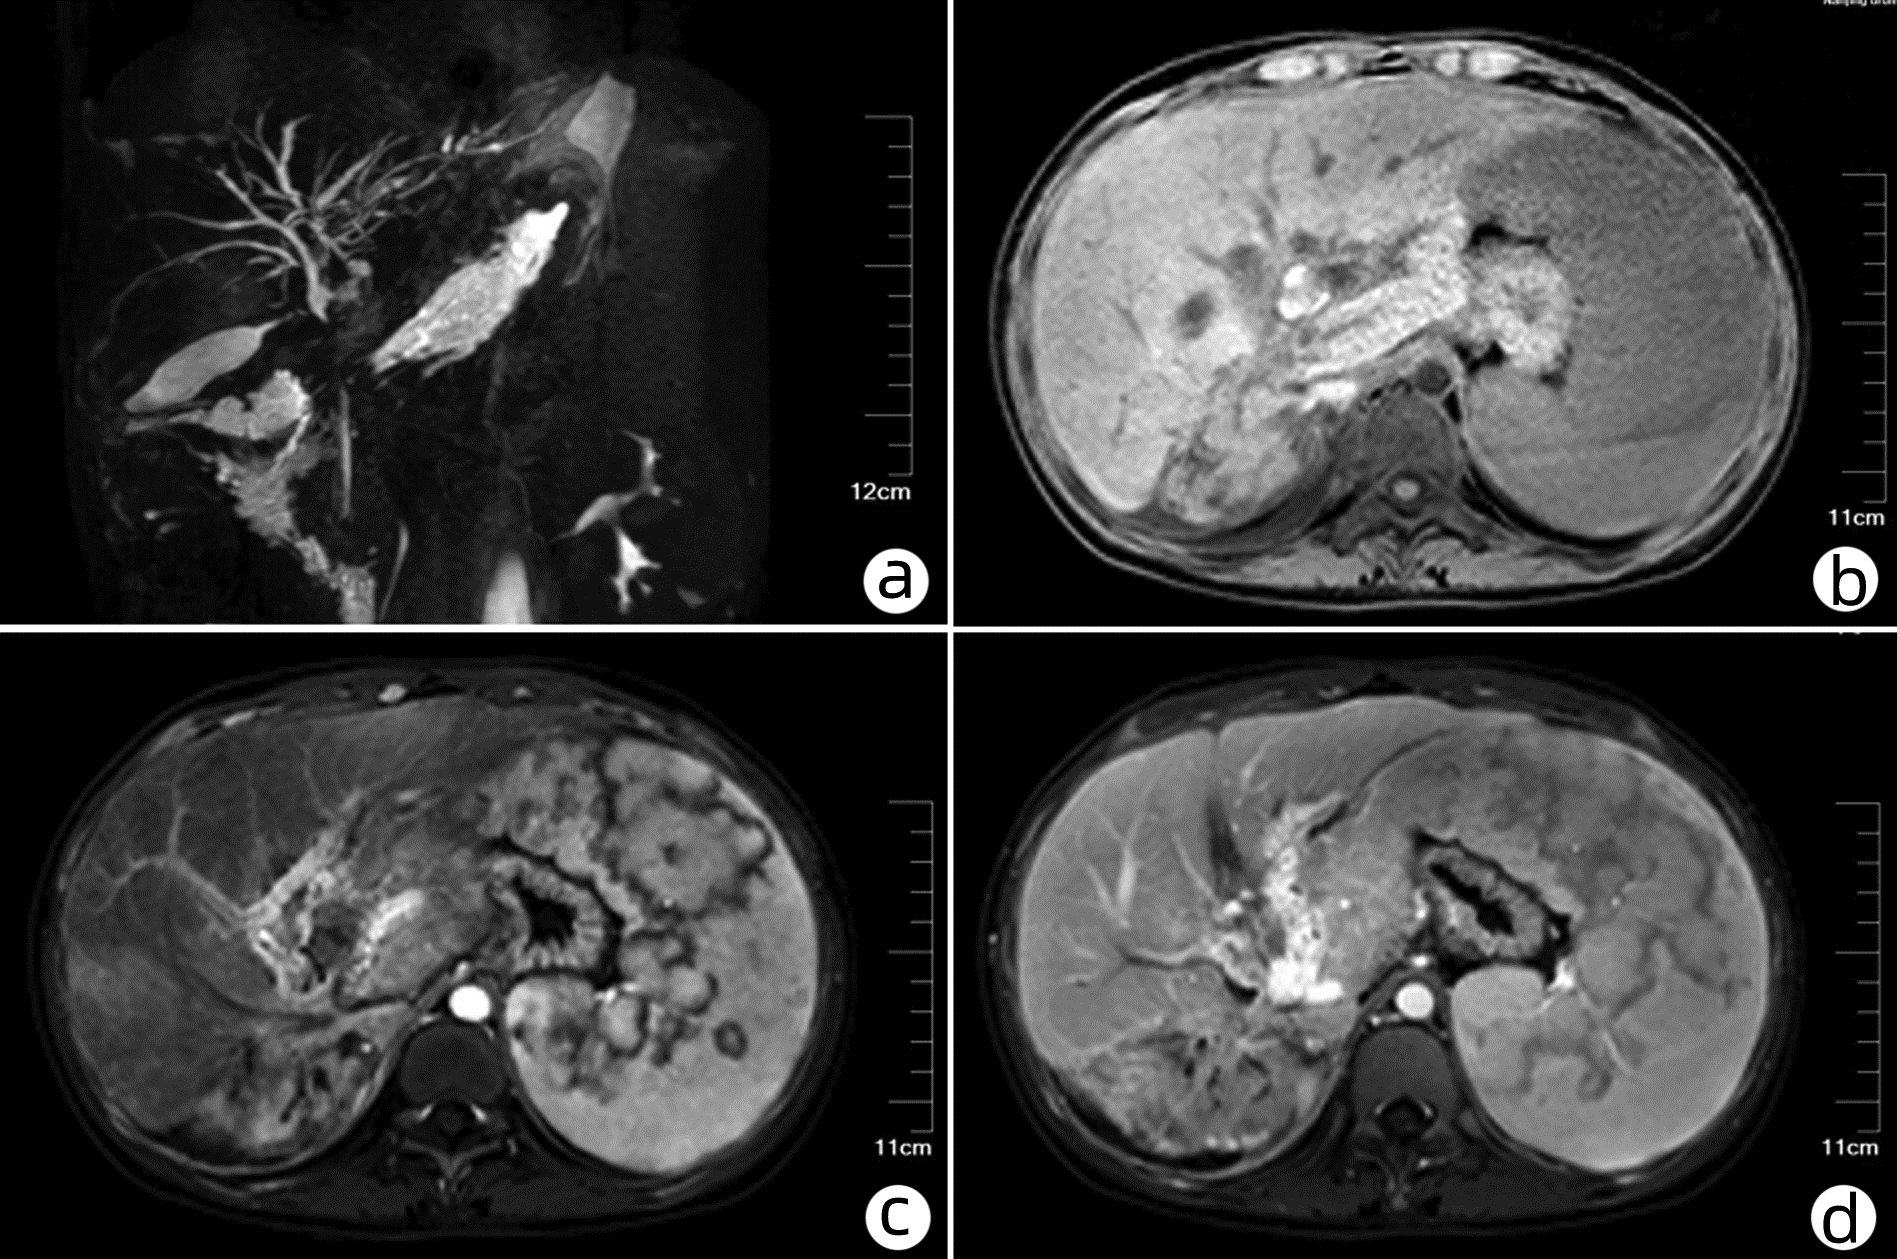

Efficacy of hepatic arterial infusion chemotherapy and its multimodality therapeutic regimens in treatment of patients with advanced hepatocellular carcinoma and related prognostic factors

Wencong DAI, Mengya ZANG, Guosheng YUAN, Qi LI, Rong LI, Wenli LI, Shuyu DONG, Jinzhang CHEN

2023, 39(7): 1592-1599. DOI: 10.3969/j.issn.1001-5256.2023.07.013

Abstract(1478) HTML (1038) PDF (2254KB)(93)

Abstract:

Objective  To investigate the efficacy of continuous hepatic arterial infusion chemotherapy (HAIC) with the FOLFOX regimen and its multimodality therapeutic regimen in the treatment of patients with advanced hepatocellular carcinoma, as well as the influencing factors for prognosis.  Methods  A retrospective analysis was performed for the clinical data of 66 patients with advanced hepatocellular carcinoma who received continuous HAIC with FOLFOX regimen in Nanfang Hospital, Southern Medical University, from September 2018 to November 2021. The patients were observed in terms of objective response rate (ORR), disease control rate (DCR), median progression-free survival (mPFS), and median overall survival (mOS) after treatment, and treatment-related adverse reactions were recorded. For the patients with portal vein tumor thrombus, the effect of the treatment on portal vein tumor thrombus was assessed. The Kaplan-Meier method was used for survival analysis, and the Cox regression analysis was used to investigate the influencing factors for prognosis.  Results  According to the RECIST1.1 criteria, FOLFOX-HAIC and its multimodality therapeutic regimen achieved an ORR of 33.3% (22/66) and a DCR of 86.4% (57/66) in the treatment of 66 patients with advanced hepatocellular carcinoma, with an mPFS time of 8.2 months and an mOS time of 22.1 months. Among the 39 patients with portal vein tumor thrombus, 2 achieved complete remission, 8 achieved partial remission, 24 achieved stable disease, and 5 had disease progression, with an ORR of 25.6% (10/39) and a DCR of 87.2% (34/39). The main adverse reactions included gastrointestinal reactions (16.7%, 11/66), pyrexia (12.1%, 8/66), liver area pain (10.6%, 7/66), bone marrow suppression (3.0%, 2/66), and contrast agent allergy (3.0%, 2/66), and there were no grade > Ⅳ toxic or side effects or deaths caused by such complications. The Cox regression analysis showed that extrahepatic metastasis (hazard ratio [HR]=2.668, 95% confidence interval [CI]: 1.357-5.245, P < 0.05) and prothrombin time (PT) (HR=1.282, 95%CI: 1.080-1.630, P < 0.05) were independent risk factors for PFS, and aspartate aminotransferase level (HR=1.008, 95%CI: 1.002-1.013, P < 0.05) and PT (HR=1.303, 95%CI: 1.046-1.630, P < 0.05) were independent risk factors for OS.  Conclusion  FOLFOX-HAIC and its multimodality therapeutic regimen has a certain clinical effect with controllable adverse reactions in the treatment of advanced hepatocellular carcinoma.